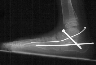

Radiographs reveal the following deformities:

- hindfoot valgus with AP talocalcaneal angle of > 35 degrees

- lateral subluxation/dislocation of the navicular from the talar head

- adduction of the metatarsals with the talus- 1st metatarsal angle to

be divergent medially

- increased lateral talocalcaneal angle with talus plantarflexed on calcaneus